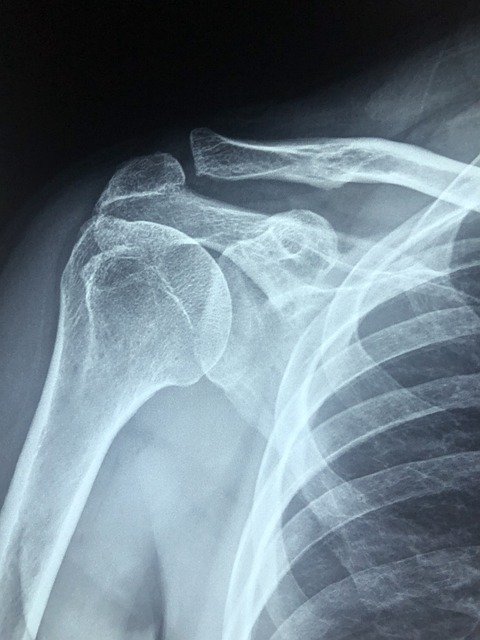

석회화 건염:명확하게 밝혀진 원인은 없지만 노화로 인해서 생기거나 힘줄에 손상이 생겨 염증이 생기거나 자극이 지속되는 경우 발생하기도 한다 합니다. 어깨 관절에 석회가 끼어 염을 유발하고 극심한 통증이 발생시키는 질환입니다. 어깨를 누르면 극심한 고통을 느끼며 팔을 들어 올리기 힘들어진다고 합니다. 어떤 사람은 통증이 있는 어깨를 누르면 테이저건에 맞은 것처럼 아프다고 말했습니다.

석회화 건염은 약물치료와 운동치료를 병행해서 치료하면 경과가 좋은 질환 중하 나입니다. 대부분의 경우 운동치료와 약물치료를 통해 증상이 호전되지만 그렇지 않은 경우 수술을 통해서 치료하는 경우도 있다고 합니다.

어깨 충돌증후군:어깨를 주로 많이 사용하는 직업을 가진 사람들에게 많이 발생하는 질환으로 알려져 있는 어깨 충돌증후군은 50대 이상의 중장년층에게서도 많이 발생합니다. 노화로 인해서 어깨가 많이 약해진 경우에도 이질환이 발생하는데 통증이 심하기 때문에 팔을 들어 올리는 것이 힘들고 심각한 경우에는 통증으로 인해서 잠을 자지 못할 정도로 힘들다고 합니다. 어깨 충돌 증후군은 대부분 약물치료와 운동치료를 통해서 치료하는 것이 일반적입니다.

회전근개 파열:어깨를 움직일 때마다 사용되는 근육과 힘줄로 이루어진 회전근개가 운동이나 충격으로 인해서 파열되어 염증이 생긴 경우 통증을 유발할 수 있으며 또는 노화로 인해서 회전근개가 파열되는 경우에 발생하는데 증상은 팔을 높이 들어 올리면 통증이 생기고 팔을 움직일 때마다 어깨 부위에서 소리가 난다면 회전근개 파열 일수 있습니다.